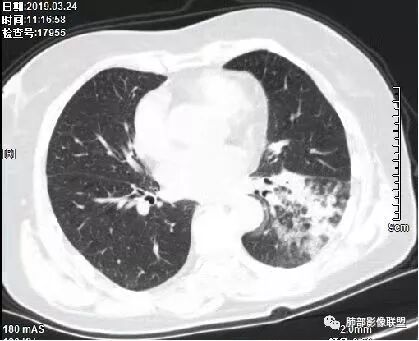

1、主病灶  左下叶斑片状、大片状致密影

2、两肺马赛克灌注

3、两侧肺门区钙化淋巴结

总共就这三大块

这三幅图是连续的,我们看到支气管中间这一幅狭窄了

大——小——大,狭窄后扩张

从这幅图看好像与周围病灶分界不清,支气管腔狭窄后扩张,支持炎性